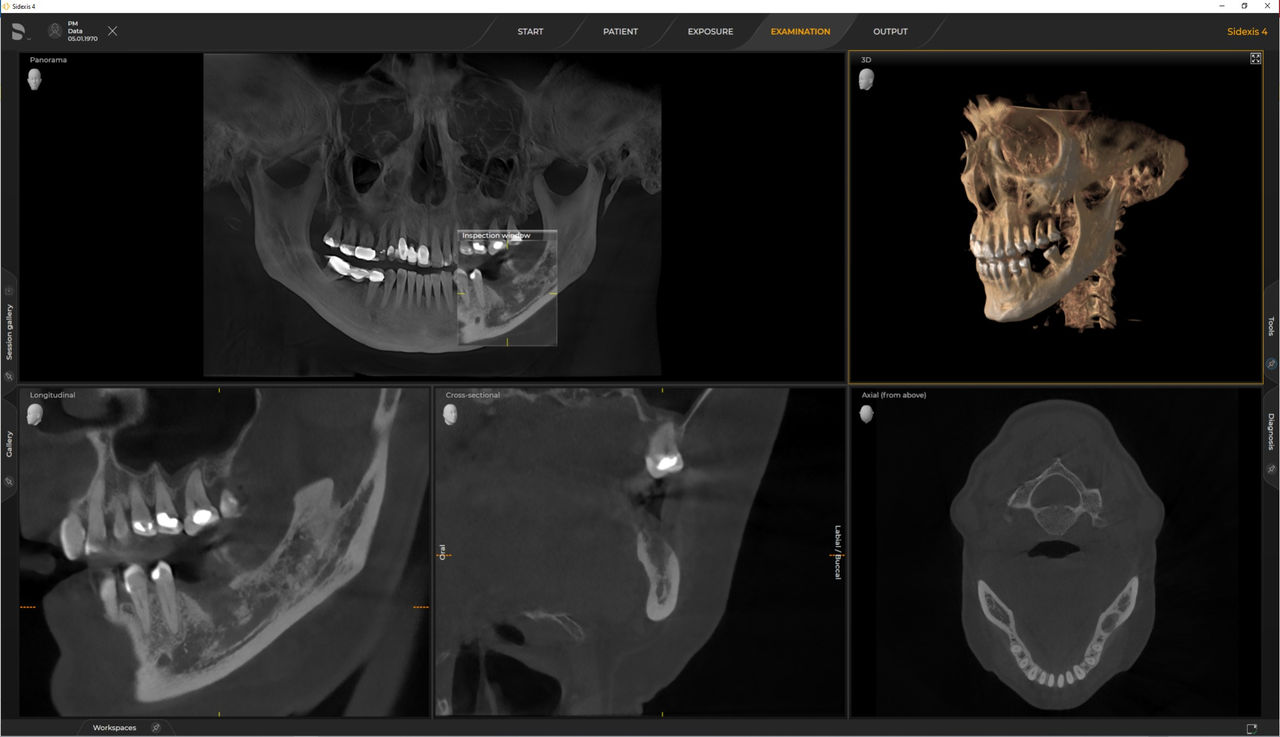

Axeos, el sistema especializado 2D/3D con un gran volumen y alta calidad de imagen para clínicas con una amplia oferta de tratamientos. Desarrollado junto a dentistas y clínicos, Axeos ofrece la gama más completa de funciones de todos los equipos de radiología extraoral de Dentsply Sirona. Además de una excelente calidad de imagen y tamaños de volumen 3D personalizados, el equipo de radiología dental está completamente optimizado para una mayor comodidad del paciente. Axeos no solo proporciona calidad en rendimiento y comodidad, sino también con su galardonado diseño gracias al cajetín de accesorios de bloque de mordida integrado y la luz ambiental.

Los numerosos tamaños de volumen garantizan la flexibilidad en la práctica diaria. Examine un área precisa o evalúe la dentición completa, lo que incluye las ATM

Las unidades 3D de Dentsply Sirona funcionan exclusivamente con Sidexis 4. Sin embargo, la migración de datos de Sidexis XG a Sidexis 4 es muy fácil. Sidexis 4 permite una experiencia digital completa con las últimas herramientas.